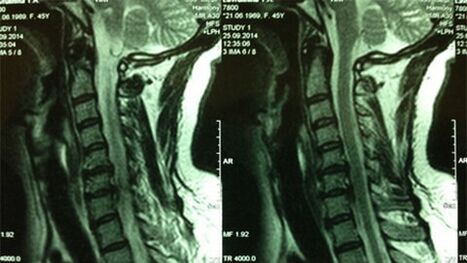

- X -Ray cervix; the MRI of the cervical department will be more informative in the initial stages of this process - it will ensure high-quality visualization of solid and soft tissues - will show the condition of the intervertebral disc, the presence of bone plants, deformation, damage to nerve roots and blood vessels; the condition of ligaments, muscles, bone tissue will be evaluated;